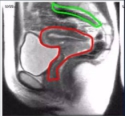

(红色部位为子宫及阴道均在放射治疗范围内)

在放射治疗过程中,阴道大部分或是全部包括在放射区域内,必然受到辐射,特别是腔内照射。